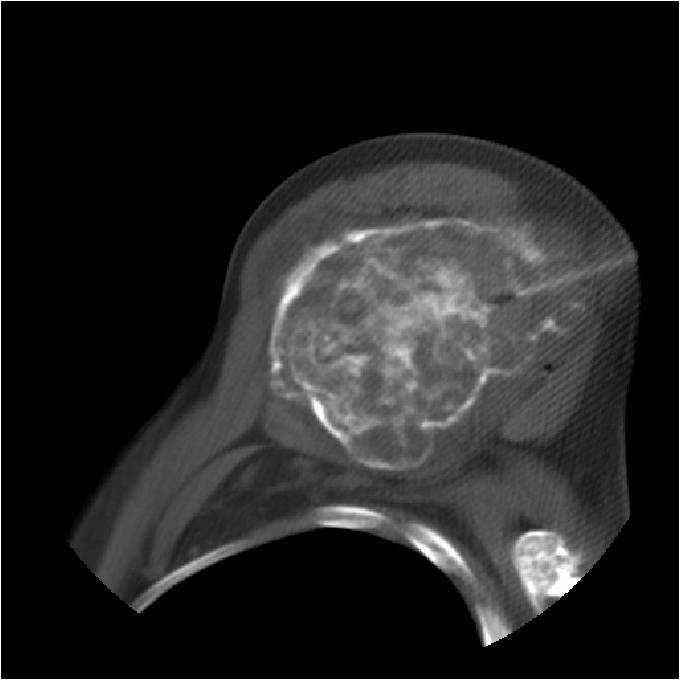

- Localized, radiolucent defect usually with punctate calcifications

- Calcifications are typical but not always present

- Matrix may demonstrate various degrees of calcification

- Calcifications are stippled, punctate, popcorn like calcifications and “Ring and Arc” calcifications

- Cartilage tumors grow in a lobular manner. The perimeters of the lobules undergo

- enchondral ossification that may calcify. If the entire perimeter of the lobule calcifies it appears

- radiographically as a “Ring”. If a portion of the perimeter of a lobule calcifies it forms an “Arc” on

- an X-ray.

- May be located centrally or eccentrically

- Geographic lytic lesion

- Central often metaphyseal in long bones

- Expansile remodeling with thinned cortex

- Chondroid matrix with calcifications in majority of tumors

- Endosteal erosion>2/3 cortical thickness on a CT scan